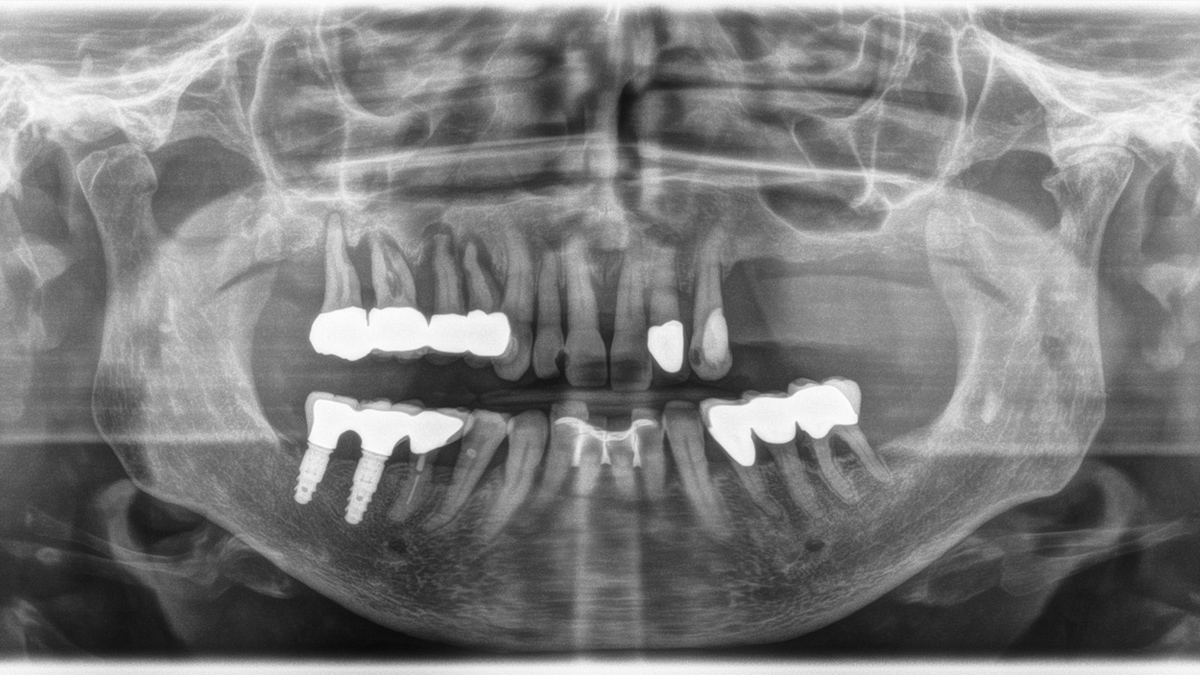

Dentition badly damaged by periodontitis, with generalized horizontal bone resorption and vertical cavities with teeth 17 – 14 requiring extraction. Hypodense, homogenous and clearly delimited changes to the hard tooth substance on 12 mesial, 11 distal and 23 mesial with suspected caries or a differential diagnosis of non-x-ray-opaque composite fillings. Differential diagnosis: Caries or non-x-ray opaque composite fillings. PFM bridge at teeth 36 – 34 due to furcation on tooth 36 and calculus deposits mesially. Splinting of teeth 32-42 from past periodontal history. Hyperdense filling material in tooth 45 without an indication for periapical lucency. Implant-based treatment in the region of teeth 46 and 47 with radiographically inconspicuous PFM hybrid bridge 45 – 47